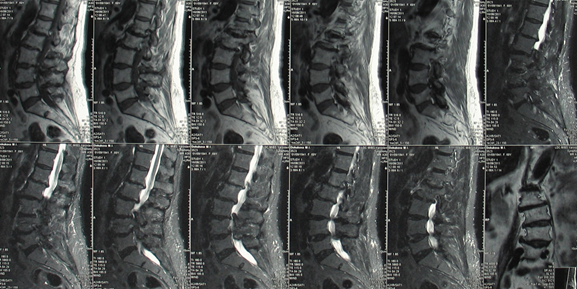

Мрт картина дегенеративно дистрофических изменений пояснично крестцового отдела позвоночника